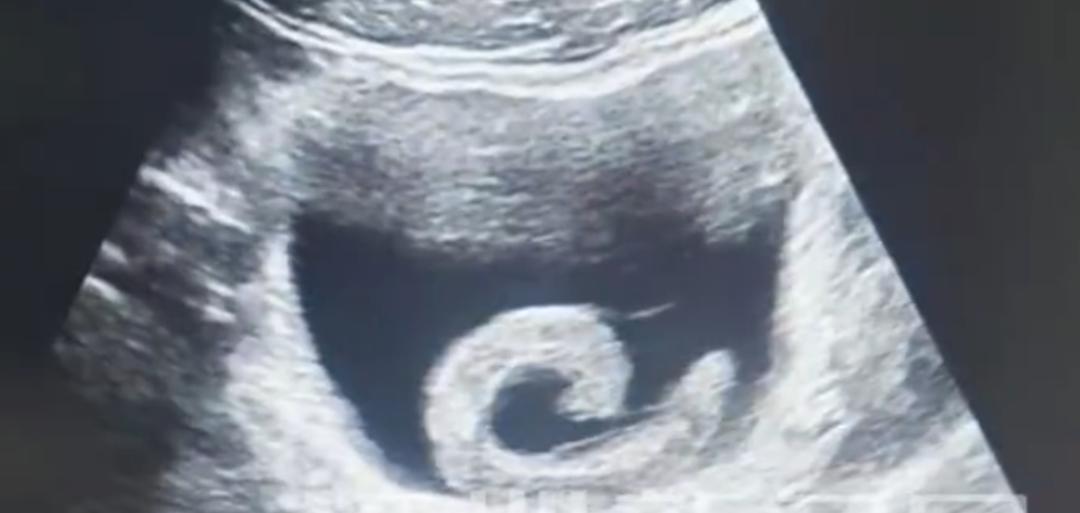

年纪轻轻,是脑袋进水了,还是脑筋跑偏了?咋还把水蛭往尿道里塞? 前不久,河南郑州23岁的小郑,在网上看到一些“偏方”传言。出于难以言喻的好奇和猎奇心理,竟然网购一条活体水蛭,将其塞入了自己的尿道。 啥叫“水蛭”?其实就是蚂蝗。 最初,小郑期待某种“奇特”的效果。但很快,剧烈的疼痛和排尿困难,就让他清醒过来了——自己做了一件很莽撞、很荒唐的傻事! 水蛭顺着尿道向内爬行,最终“安家”在膀胱,开始疯狂吸血,并且释放抗凝血物质。 小郑痛苦不堪,实在无法忍受了!最后只得求助医生,经手术将水蛭取出……